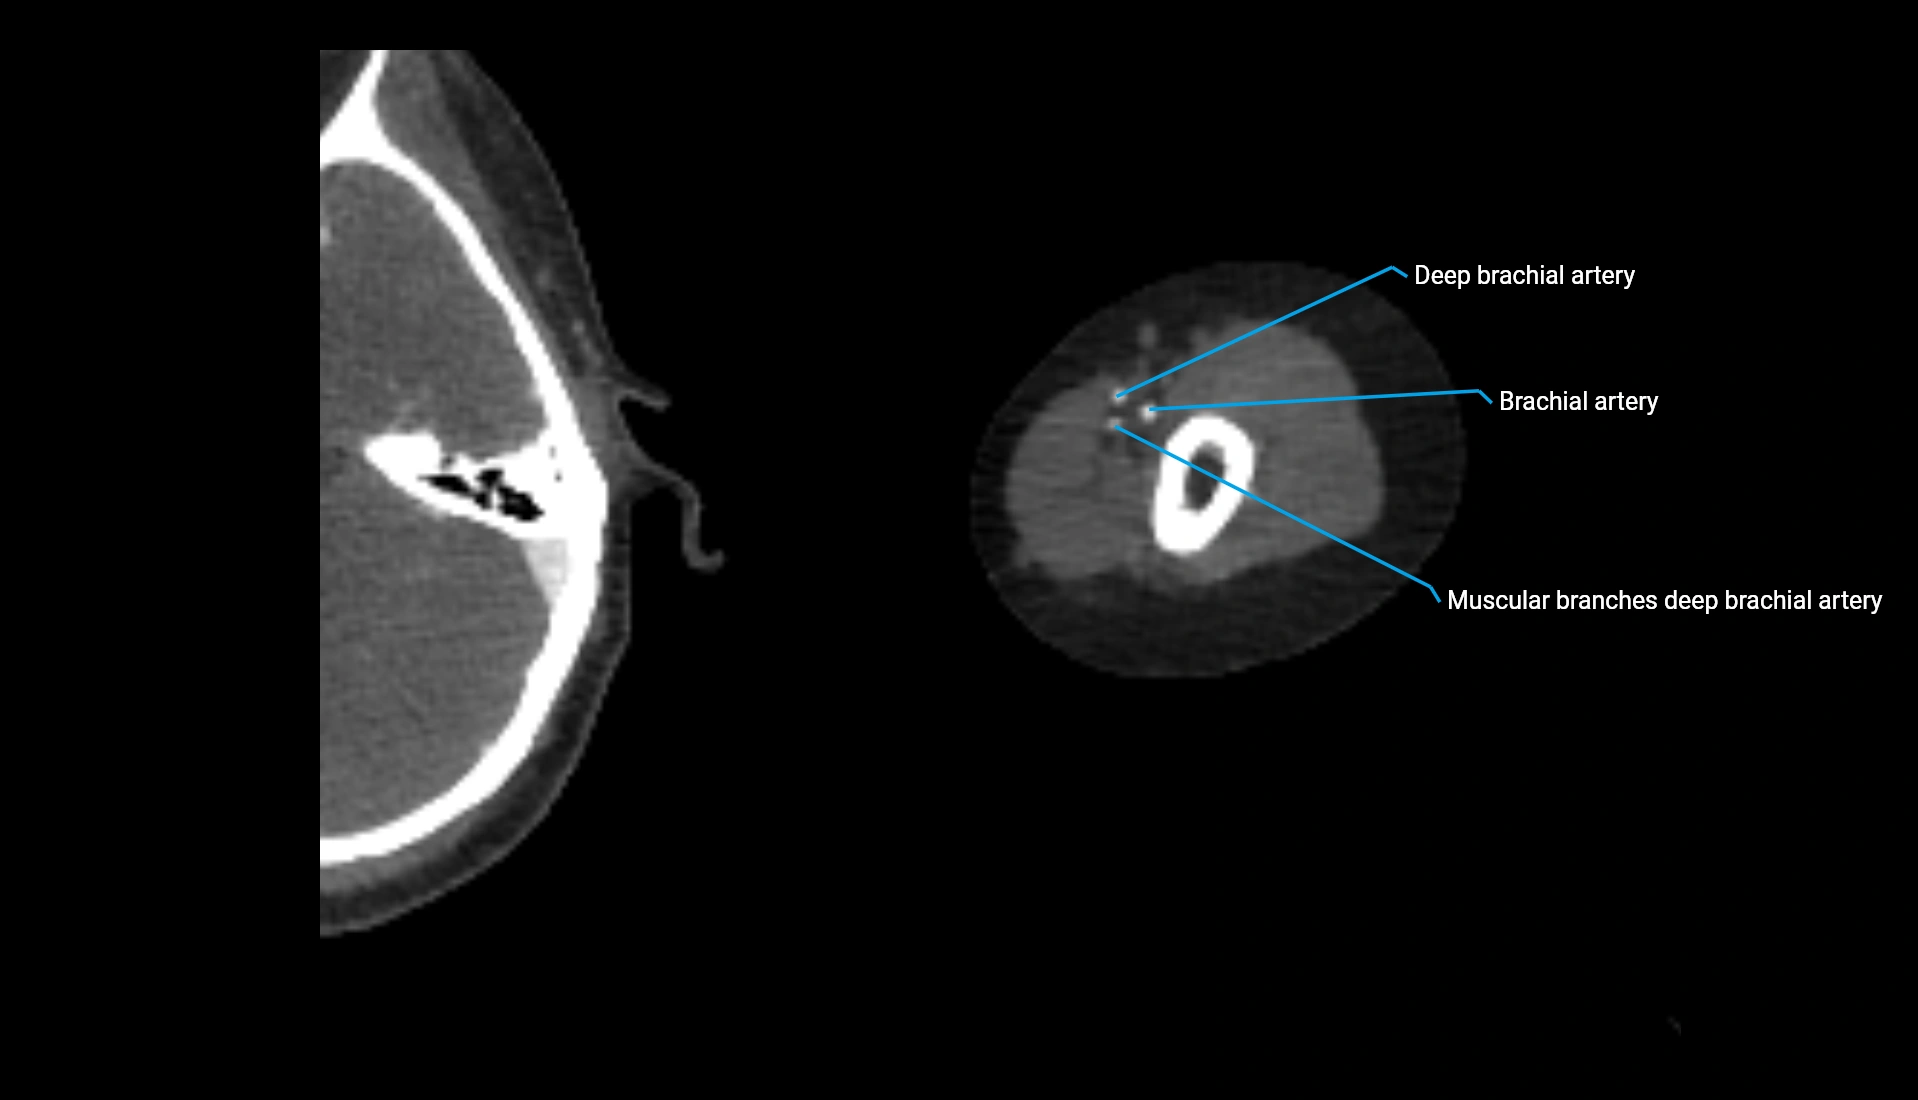

CT Appearance

Non-Contrast CT:

• Cortex: High-density, sharply defined

• Subchondral bone: Dense cancellous matrix

• Articular surface: Smooth concave contour articulating with the capitellum

• Excellent for evaluating bone integrity, alignment, and subtle fractures

Post-Contrast CT:

• Bone: No enhancement

• Joint capsule and synovium: Mild enhancement outlining the joint

• Improves contrast between soft tissues and bony margins

• Useful in detecting subtle joint abnormalities or postoperative changes